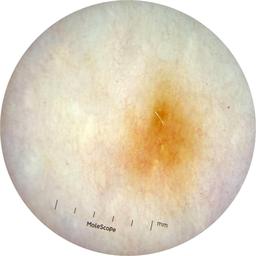

MEL-SELF - Dermoscopic

- Name: MEL-SELF - Dermoscopic

Description:

Dermoscopic lesion images (close-up views of benign and malignant lesions) from the MEL-SELF trial (the Melanoma Self Surveillance trial).